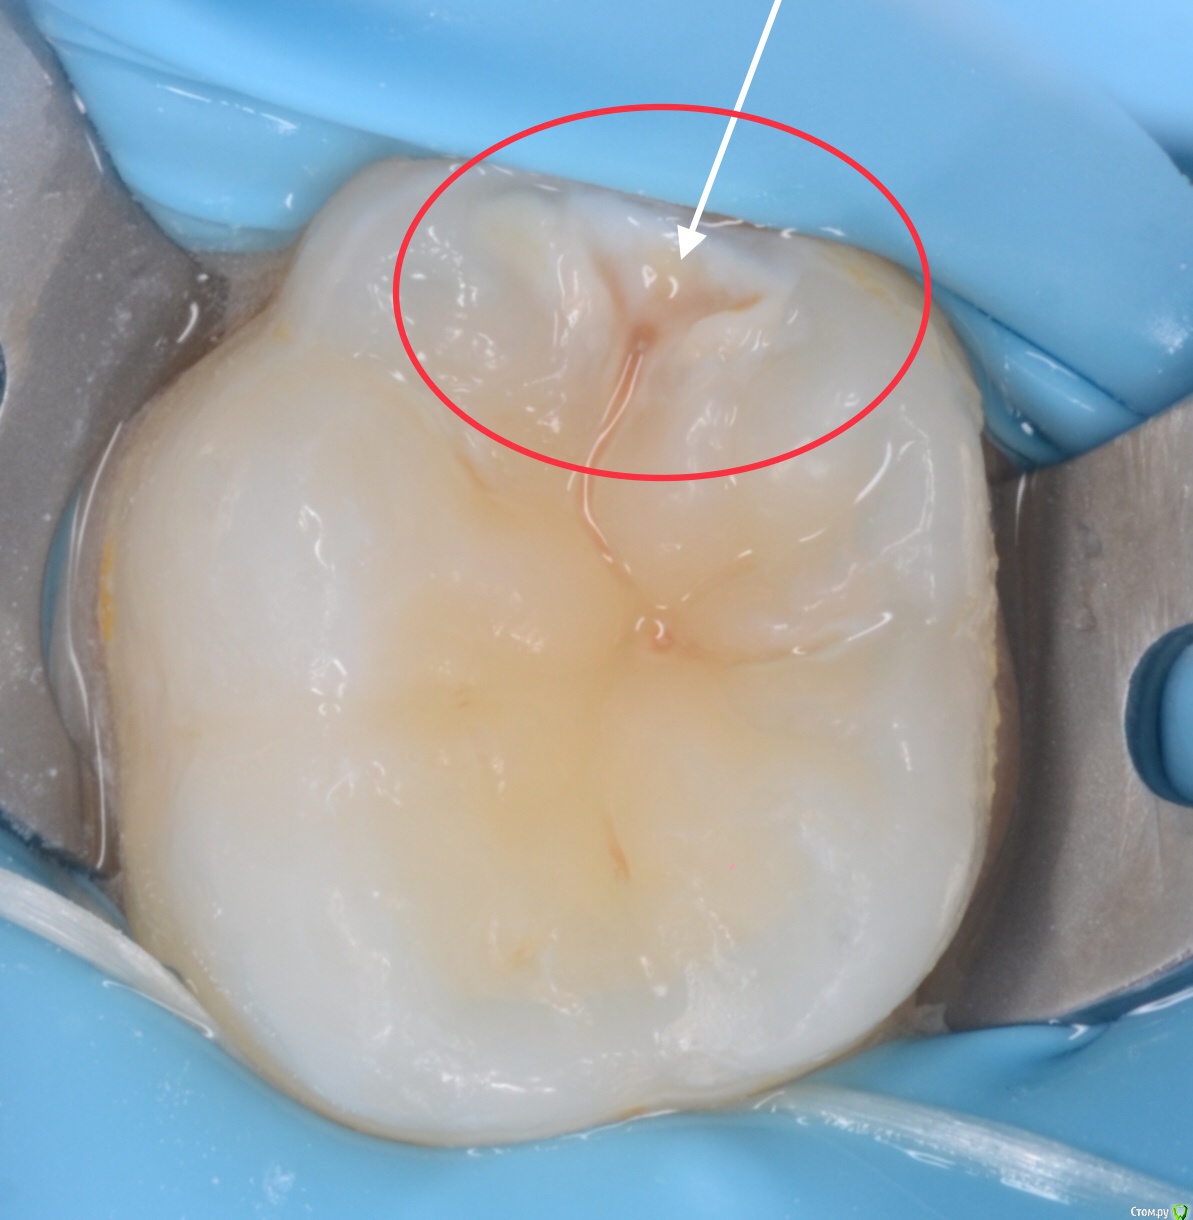

CRAZYDUCK Опубликовано 14 июня, 2018 Автор Поделиться Опубликовано 14 июня, 2018 Очередная история про скрытый кариес . Все зубы пролечили и успокоились . Пропали на год -два . А кариес растёт и радуется . Коллеги ,часто так бывает ? Часто . Но не в этом случае . Осмотр спустя 7 месяцев помог выявить скрытую кариозную полость на 5.5 зубе . RVG ( хочу diagnocam Ссылка на комментарий